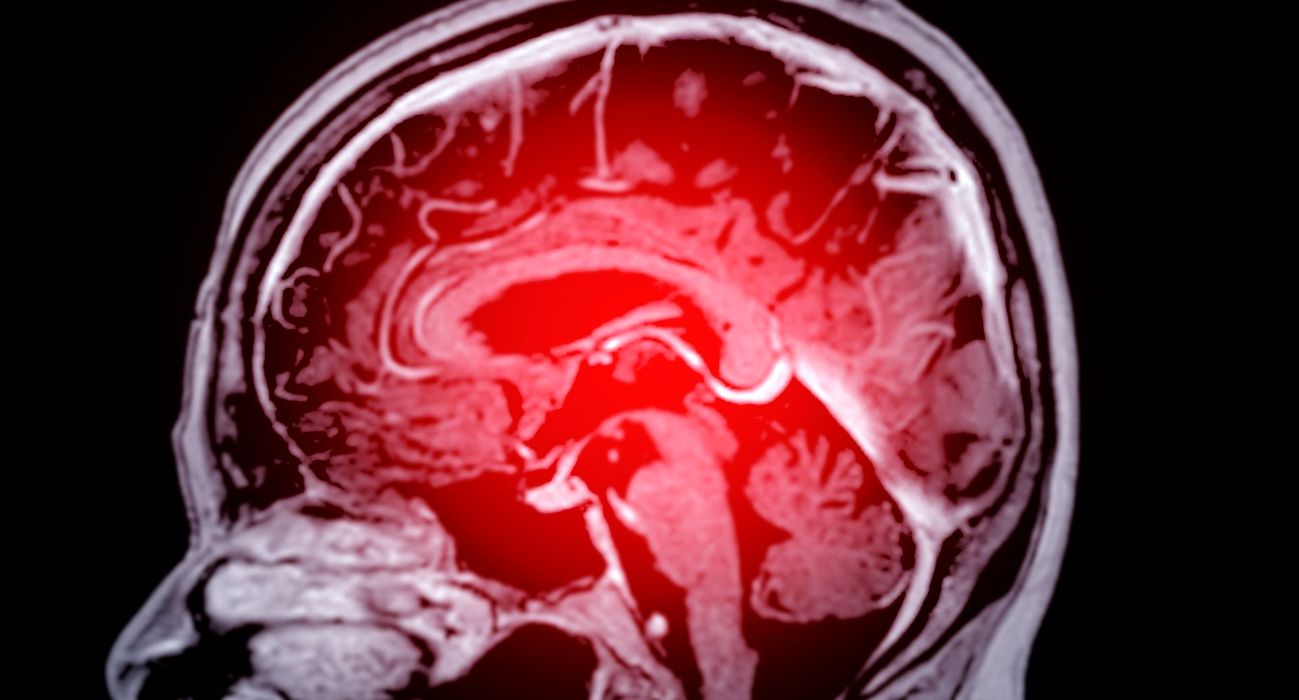

Oamenii de știință ar fi la un pas să rezolve un obstacol major în tratarea creierului

Una dintre cele mai mari provocări în livrarea tratamentelor pentru Alzheimer și alte boli legate de creier este depășirea sistemului robust de apărare pe care creierul îl are pentru a se proteja. Însă, datorită unui […]